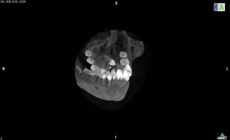

●歯科用CT(埋伏歯の牽引や顎変形症の診断 保険外)

歯が骨の中に埋もれていたり、補綴(ブリッジやインプラント)治療と併用した治療になる場合、追加検査をすることがあります。